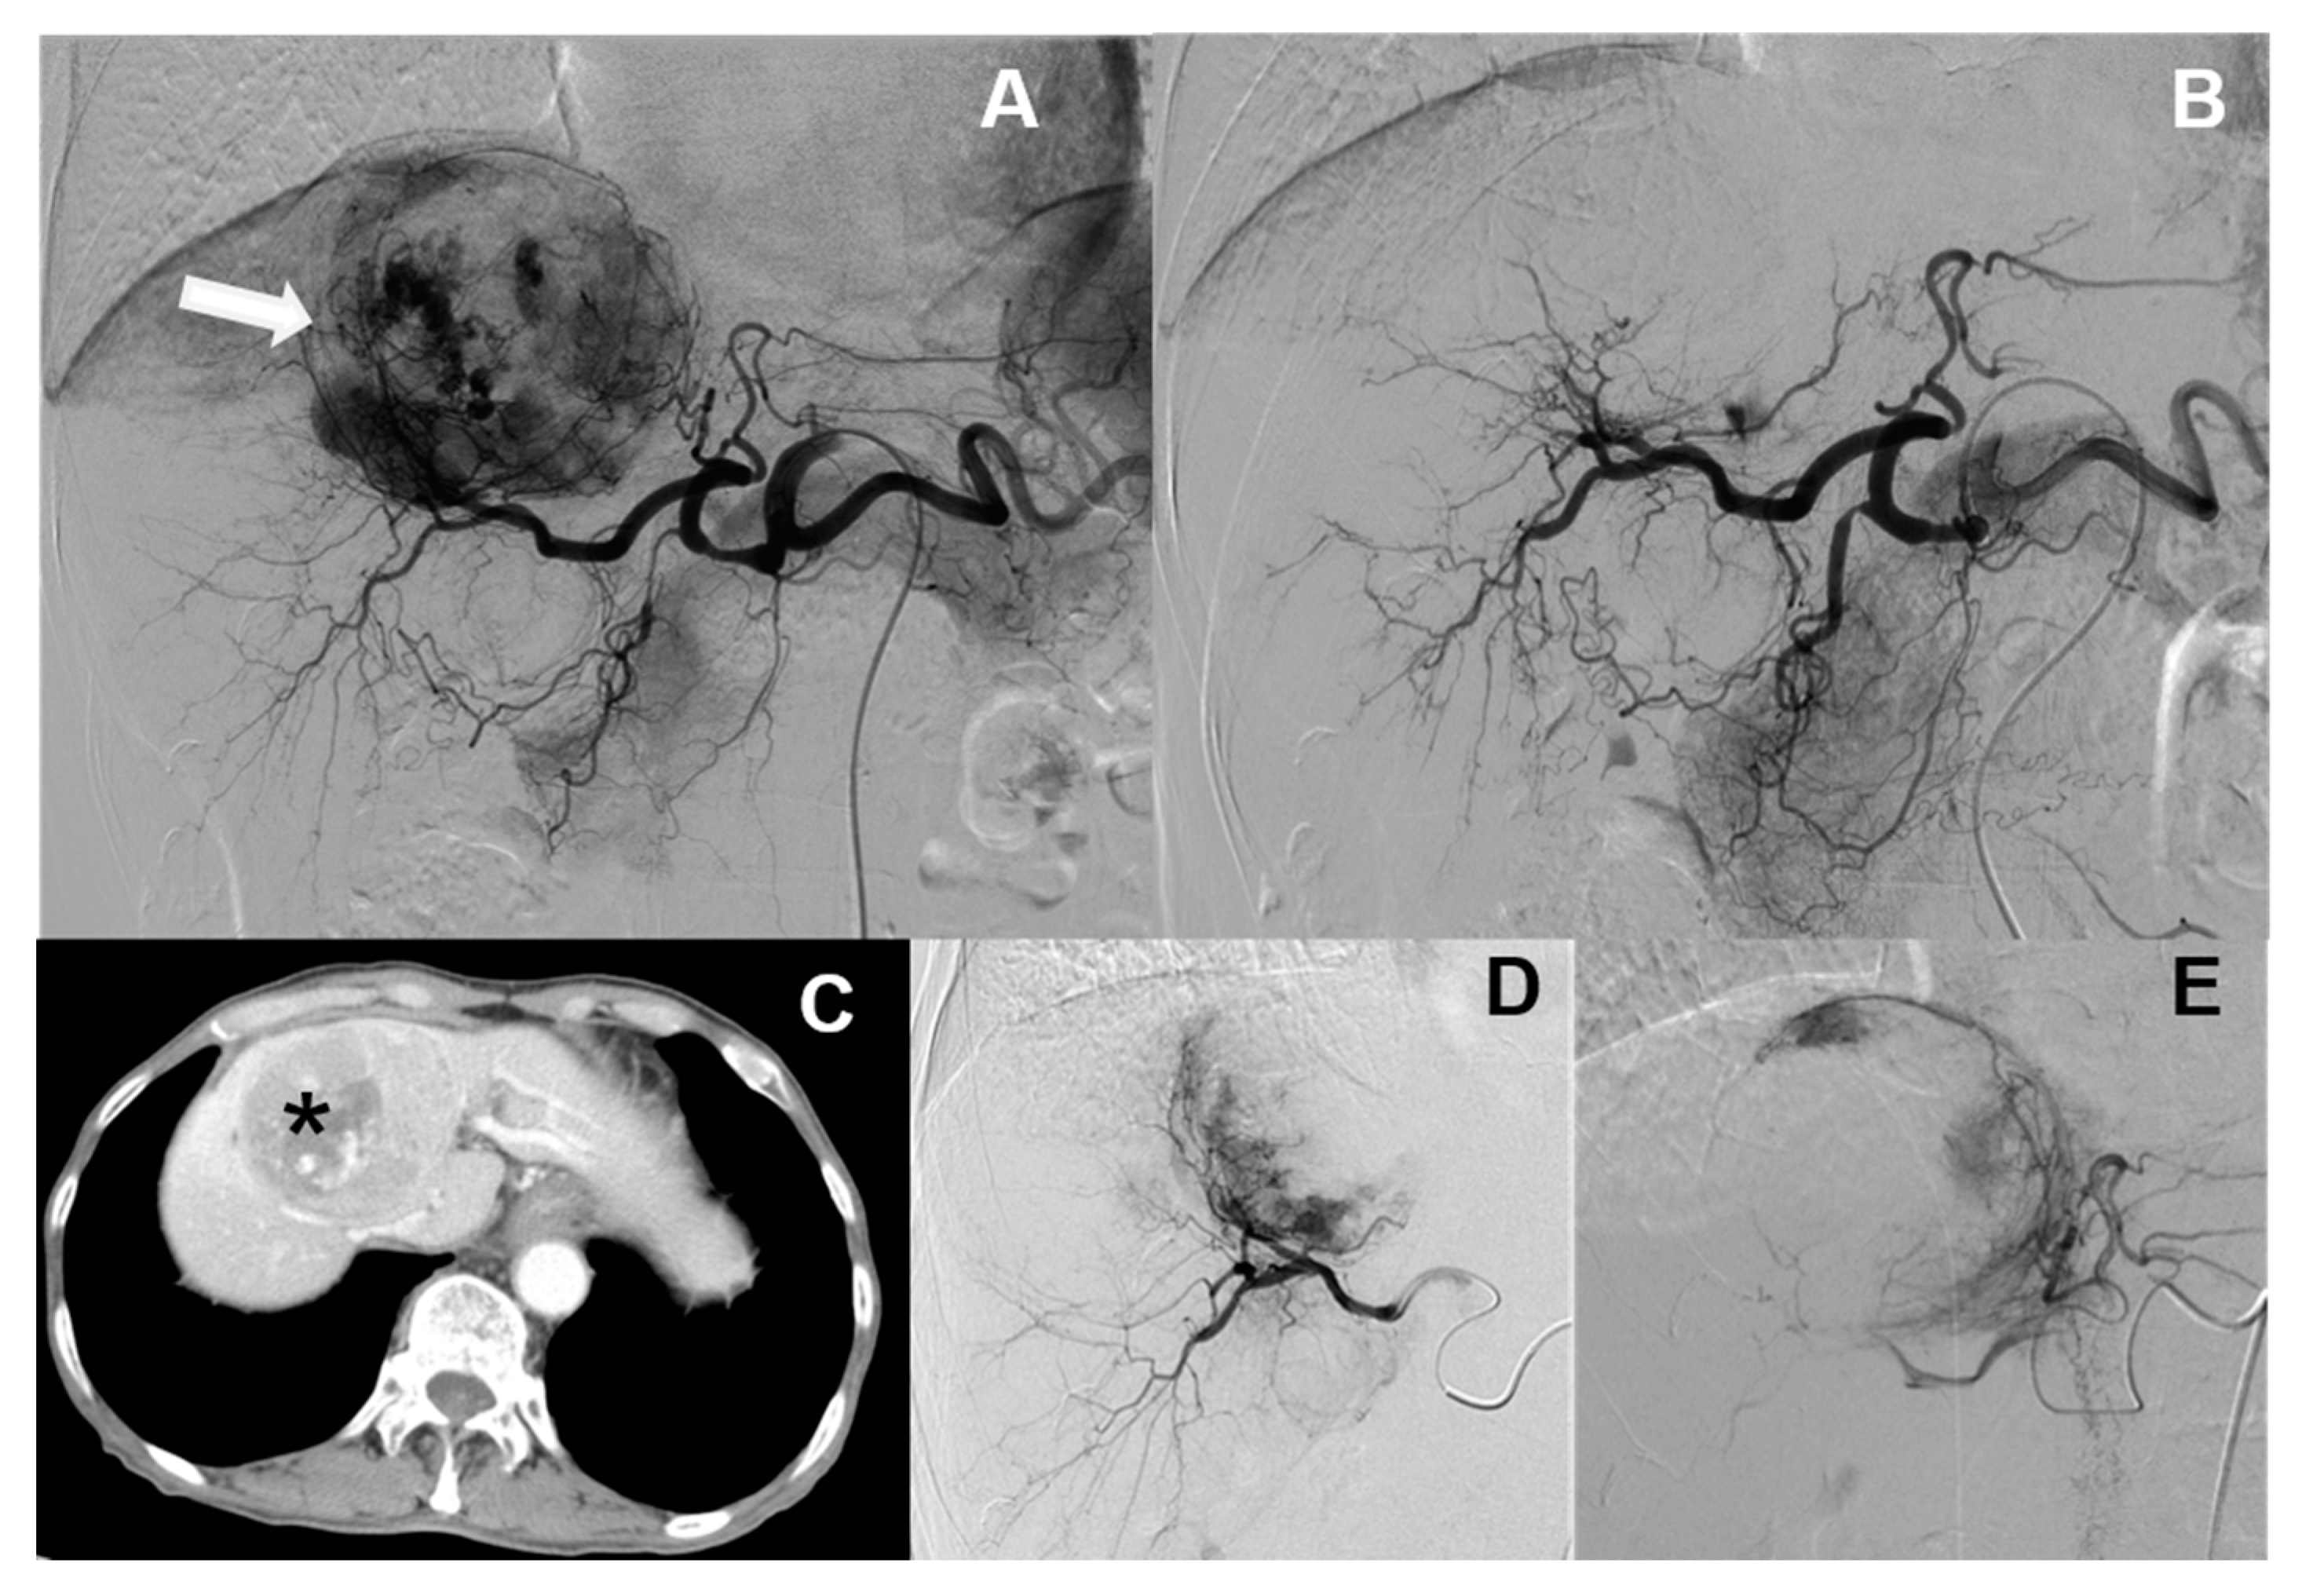

Currently, hepatic artery embolization is performed using two main treatment methods, both involving trans-catheter arterial chemoembolization (“TACE”). Conventional trans-catheter arterial chemoembolization (“cTACE”) is the older of the two methods (Figure 1), whereas microsphere-loaded arterial embolization—called “DC bead TACE”, after the drug-eluting microbeads employed—is the newer (Figure 2). DC bead TACE involves the use of a microsphere-loaded drug that prolongs effective treatment times and results in better therapeutic outcomes [2]. Compared with cTACE, DC bead TACE results in better therapeutic response and delayed tumor progression; however, no significant difference has been noted in liver-related toxicity. Song et al. demonstrated the superior performance of arterial embolization performed using DC beads [3], and Ashrafi et al. indicated that DC bead TACE can result in the same tumor response as cTACE [4]. Although the latter study combined the clinical effectiveness of DC beads with that of cTACE, additional large-scale randomized controlled trials are still needed.

Figure 1.

Traditional embolization (cTACE). Hepatocellular carcinomas (HCC) with arterial enhancement in segment 7 of the liver in both CT images (A and B, * star) and angiography (C, white arrows). TACE is performed by using conventional TACE with lipiodol accumulation (D and E, black arrows) on follow up CT.